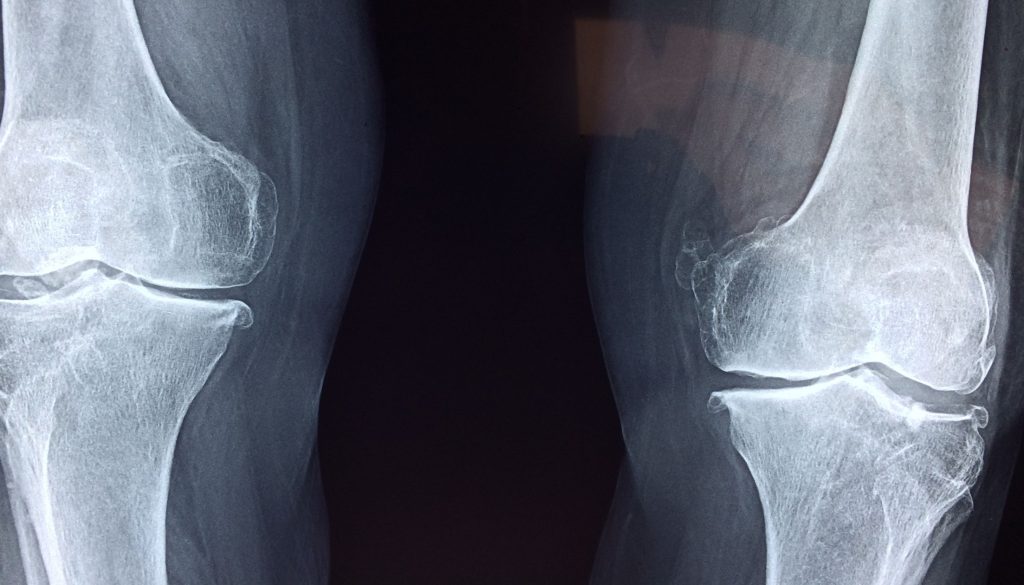

إجراء الفحوصات المنتظمة يمكن أن يكون مفتاحًا للكشف المبكر عن أي مشاكل في العظام. اختبارات كثافة العظام تساعد في تشخيص هشاشة العظام وتحديد خطر الكسور. إذا كنت في مجموعة خطر عالية، مثل النساء فوق سن الخمسين، قد يكون من الأفضل إجراء هذه الفحوصات بشكل دوري.